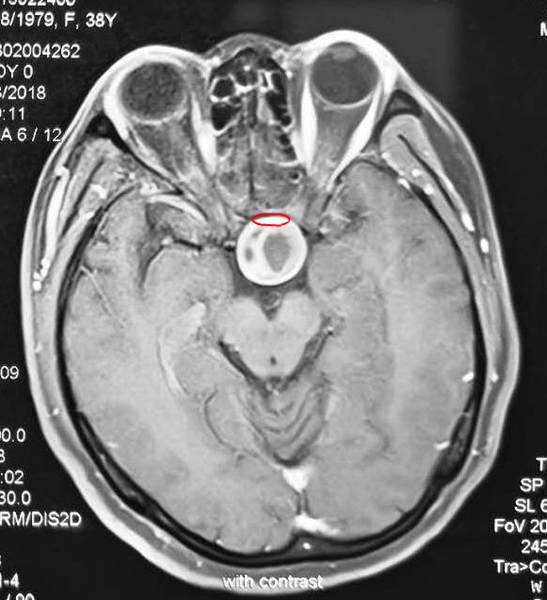

术前,垂体受肿瘤挤压变得菲薄

据袁贤瑞教授介绍,患者来医院时,她脑中的垂体已被巨大的垂体腺瘤挤压得薄如纸片,垂体柄也被挤压移位,头疼头晕,左眼颞侧出现偏盲。于是,袁贤瑞教授根据患者的手术指征,选定改良扩大经蝶窦入路,仅一个多小时将垂体腺瘤取净,垂体保留完好。